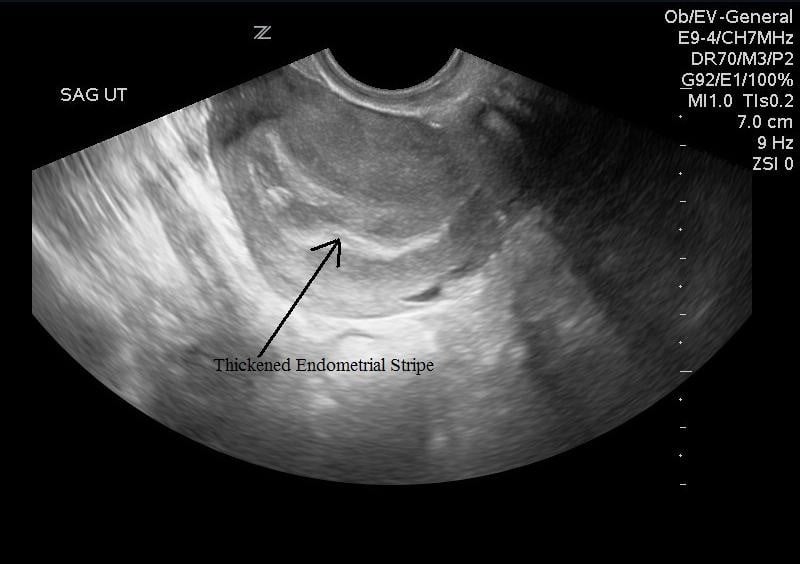

Sonoguide // Early Pregnancy

From www.acep.org

Sonoguide // Early Pregnancy What Causes On And Off Bleeding After Abortion Following a surgical abortion, you may not bleed much — or at all — the first few days. The bleeding should reduce every day. Medical abortion appears to cause more bleeding than surgical abortion, lasting an average of nine days. Bleeding may be spotty, dark. This is caused by leftover pregnancy tissue that hasn’t been. If that's the case, the. What Causes On And Off Bleeding After Abortion.